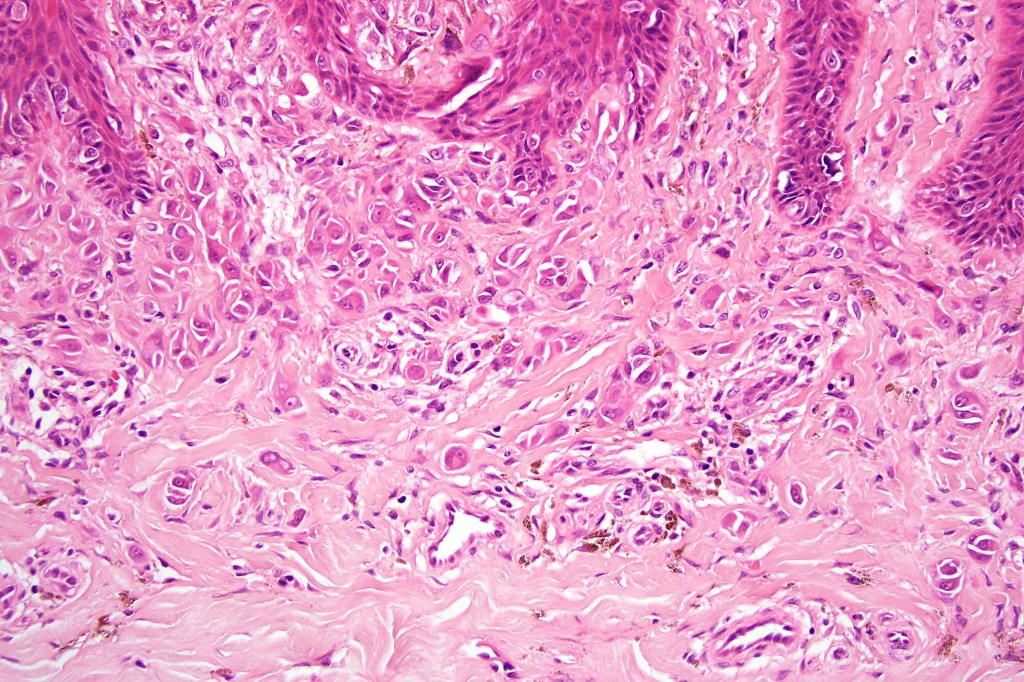

•Matures with depth-often best recognized at scanning/low power magnification & readily confirmed with S100 or MART1

•Maturation implies nest size and cell size diminishing with depth, at the base, the infiltrate may have a single cell infiltrating pattern

•Superficial vascular ectasia very frequently present

•Junctional nests often vertically orientated, dyscohesive with a surrounding retraction artifact

•Spindle cell nests often display a “raining down” growth pattern

•Spindle cells have abundant cytoplasm and vesicular nuclei with small nucleoli